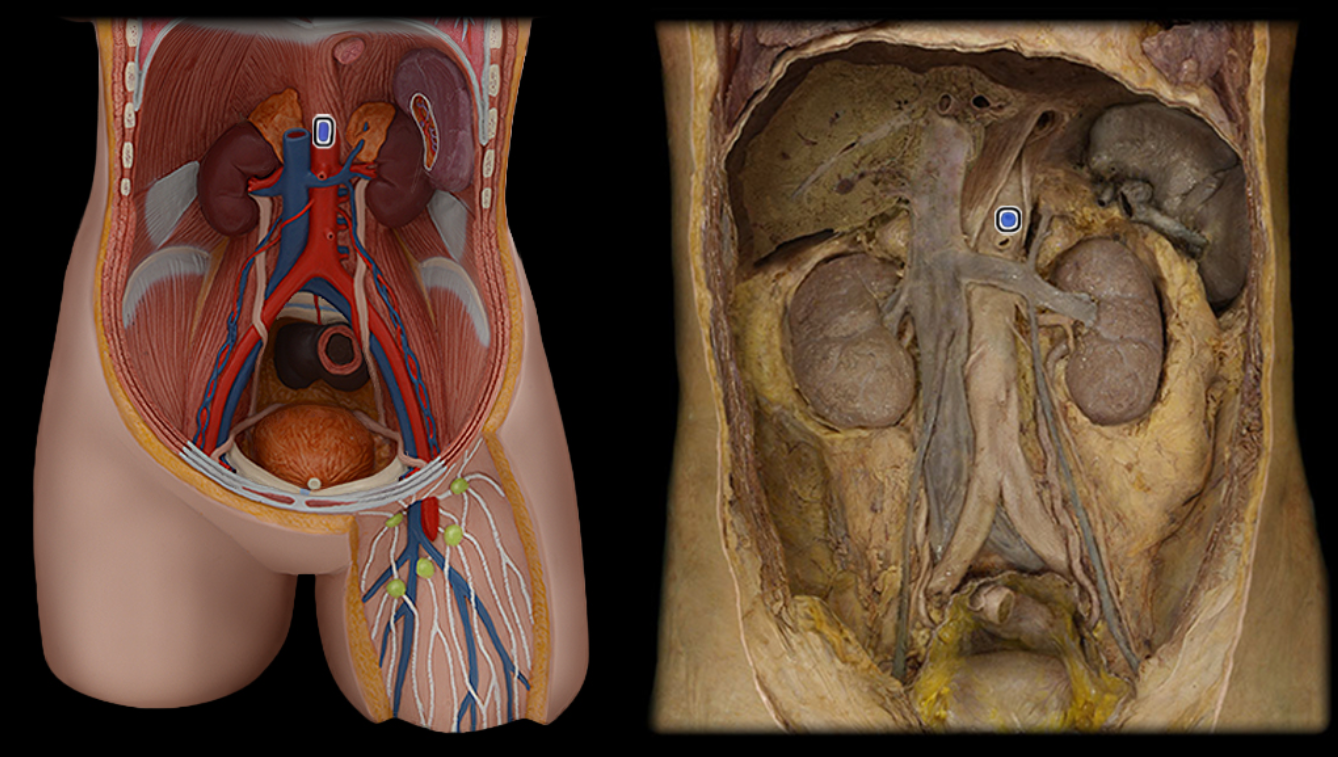

Abdominal aorta

Common iliac a.

Common iliac v.

External iliac a.

External iliac v.

Femoral a.

Femoral v.

Gonadal a.

Gonadal v.

Inferior vena cava

Renal a.

Renal v.

Superior mesenteric a.